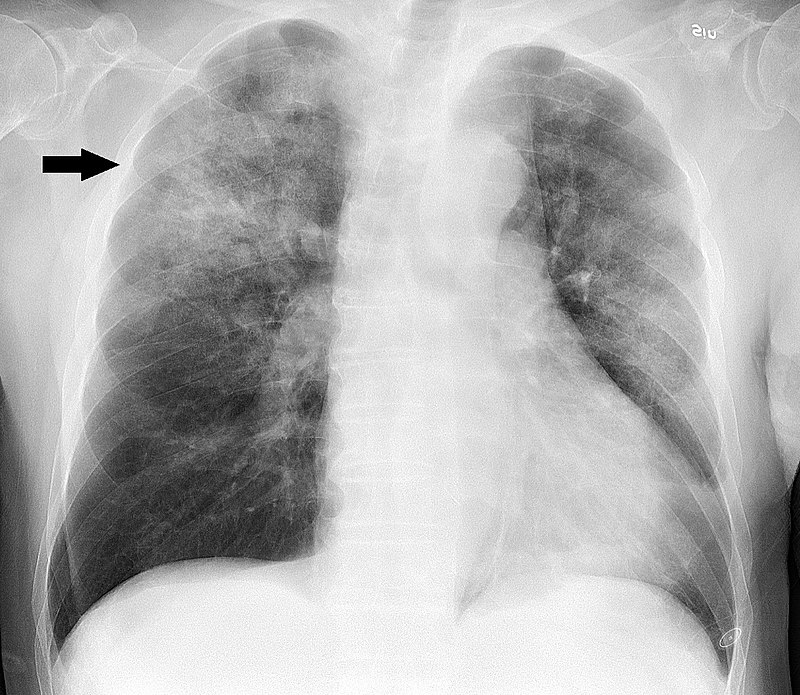

Three common patterns of pneumonia may be detected on chest X-ray which include:

- Bronchopneumonia

Bronchopneumonia

Bronchopneumonia is characterized by patchy, sporadic consolidation, concentrated on the bronchioles.

Bronchopneumonia is frequently bilateral and multifocal.

Bronchopneumonia is caused by different bacterial species.